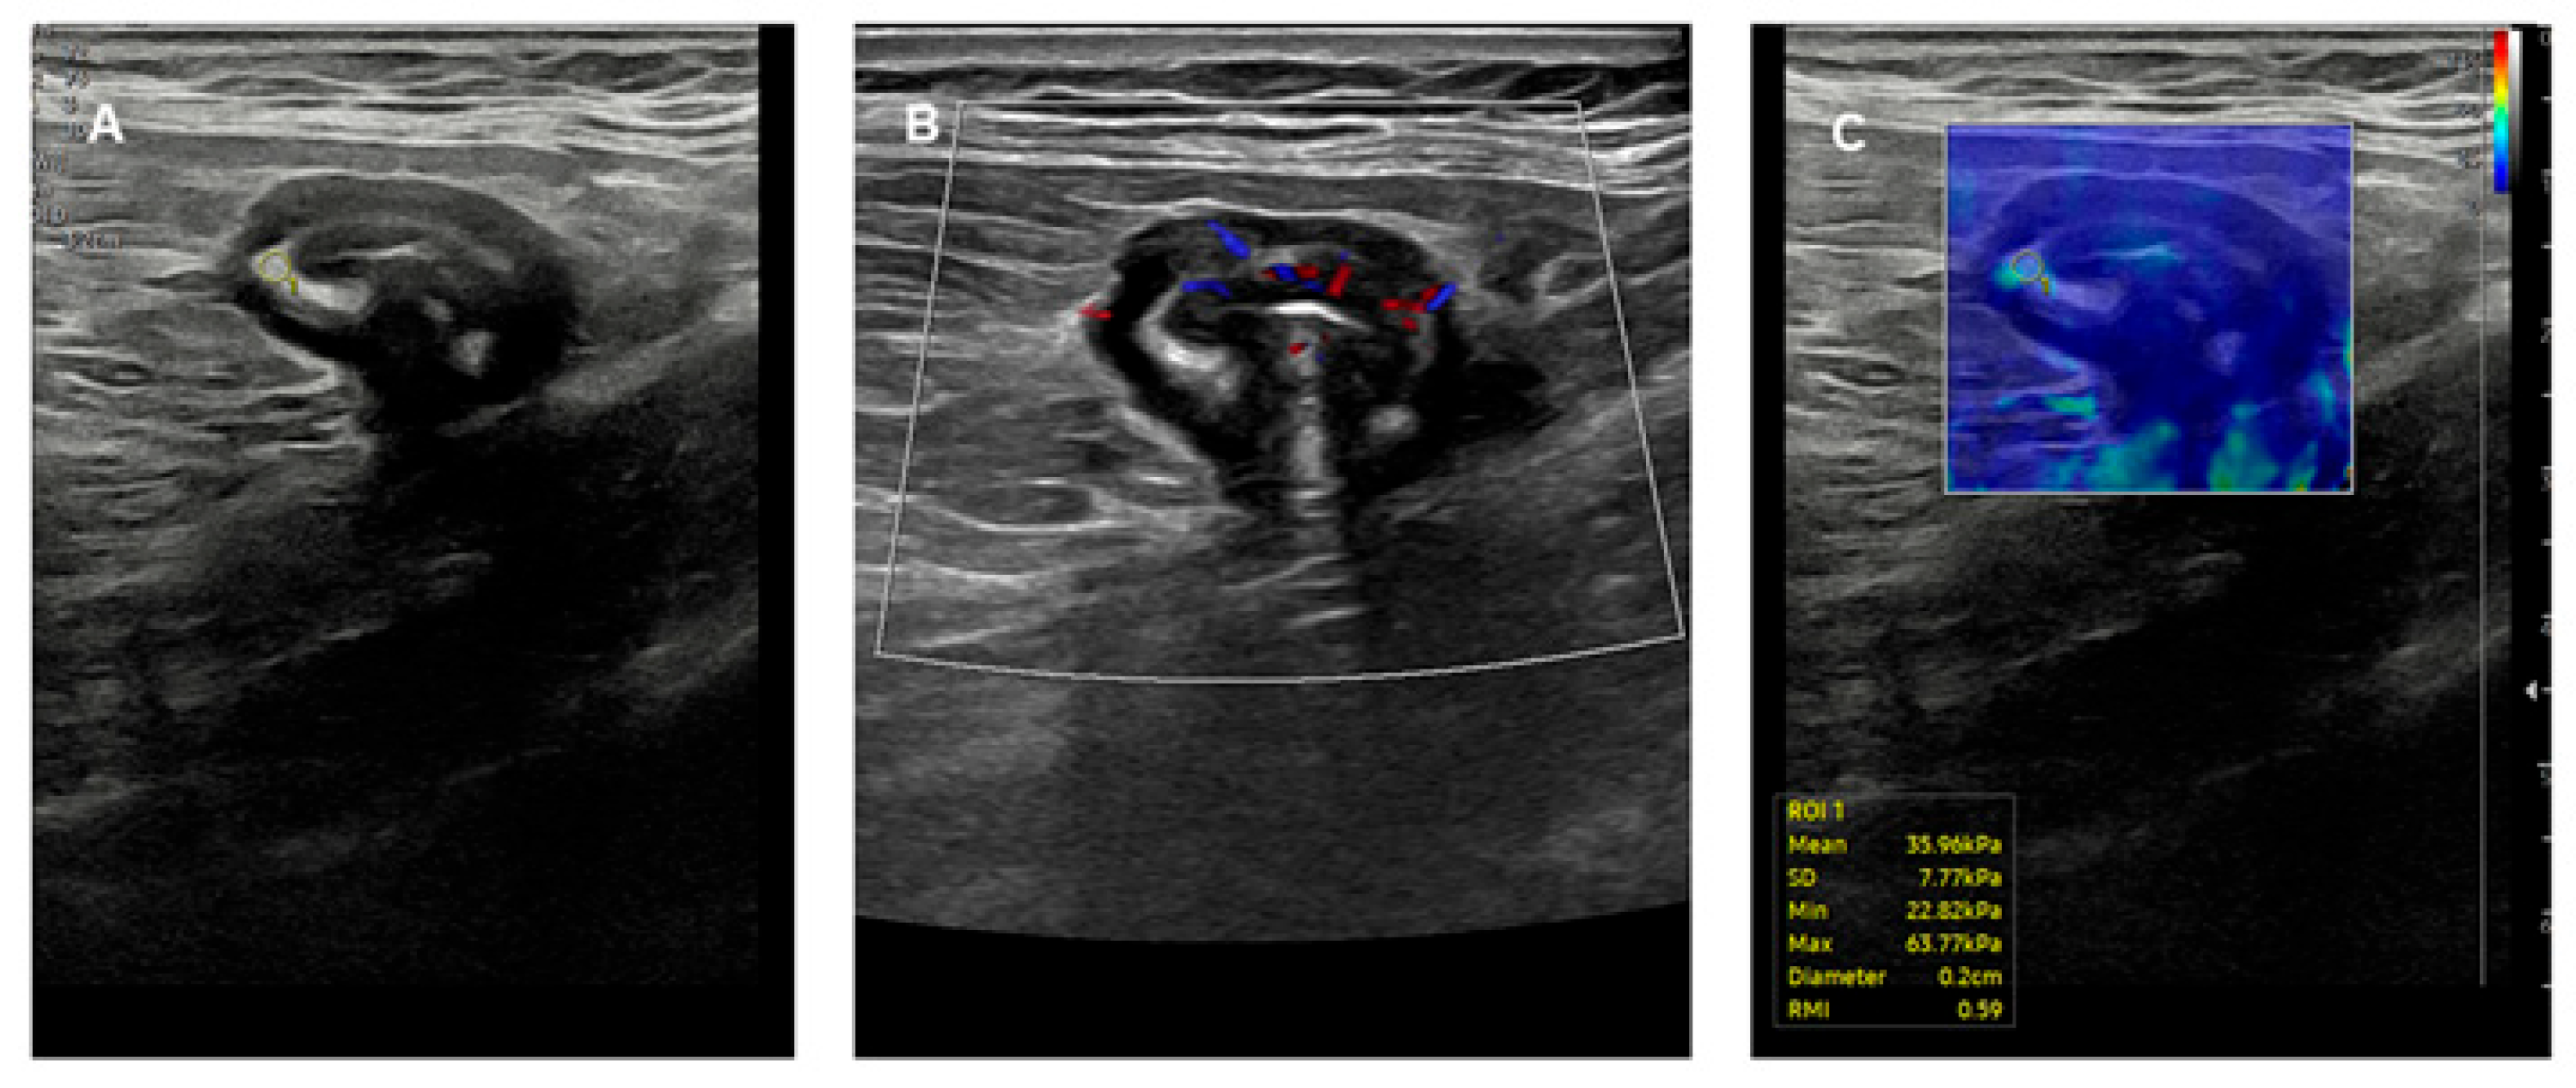

- Zhu, F.; Chen, X.; Qiu, X.; Guo, W.; Wang, X.; Cao, J.; Gong, J. Seeing beyond the surface: Superior performance of ultrasound elastography over Milan ultrasound criteria in distinguishing fibrosis of ulcerative colitis. J. Crohn’s Colitis 2024, 18, 1795–1803. [Google Scholar] [CrossRef]

- Yamada, K.; Ishikawa, T.; Kawashima, H.; Ohno, E.; Iida, T.; Ishikawa, E.; Mizutani, Y.; Sawada, T.; Maeda, K.; Yamamura, T.; et al. Evaluation of ulcerative colitis activity using transabdominal ultrasound shear wave elastography. Quant. Imaging Med. Surg. 2022, 12, 618–626. [Google Scholar] [CrossRef]

- Rustemovic, N.; Cukovic-Cavka, S.; Brinar, M.; Radić, D.; Opacic, M.; Ostojic, R.; Vucelic, B. A pilot study of transrectal endoscopic ultrasound elastography in inflammatory bowel disease. BMC Gastroenterol. 2011, 11, 113. [Google Scholar] [CrossRef] [PubMed]